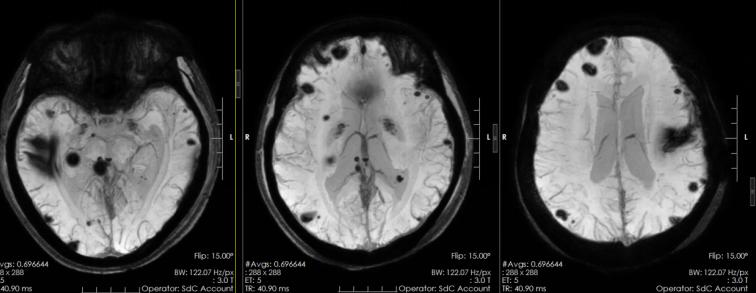

我院完善颅脑MR检查后,明确患者为左侧额叶病灶存在出血。进一步完善脑电图等检查,经科室讨论,考虑患者为颅内多发海绵状血管瘤。“病灶位置多达十几处,位置比较分散,一次手术无法全部清除。”神经外六科主任吴杰分析,病灶虽多,但只有左额叶病灶伴有出血,且该病灶为致痫灶,有手术适应症。

术前头颅MRI:颅内多发海绵状血管瘤